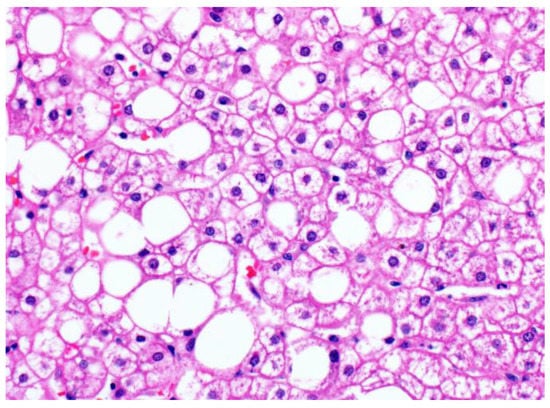

3.2. Glycogenosis in NAFLD